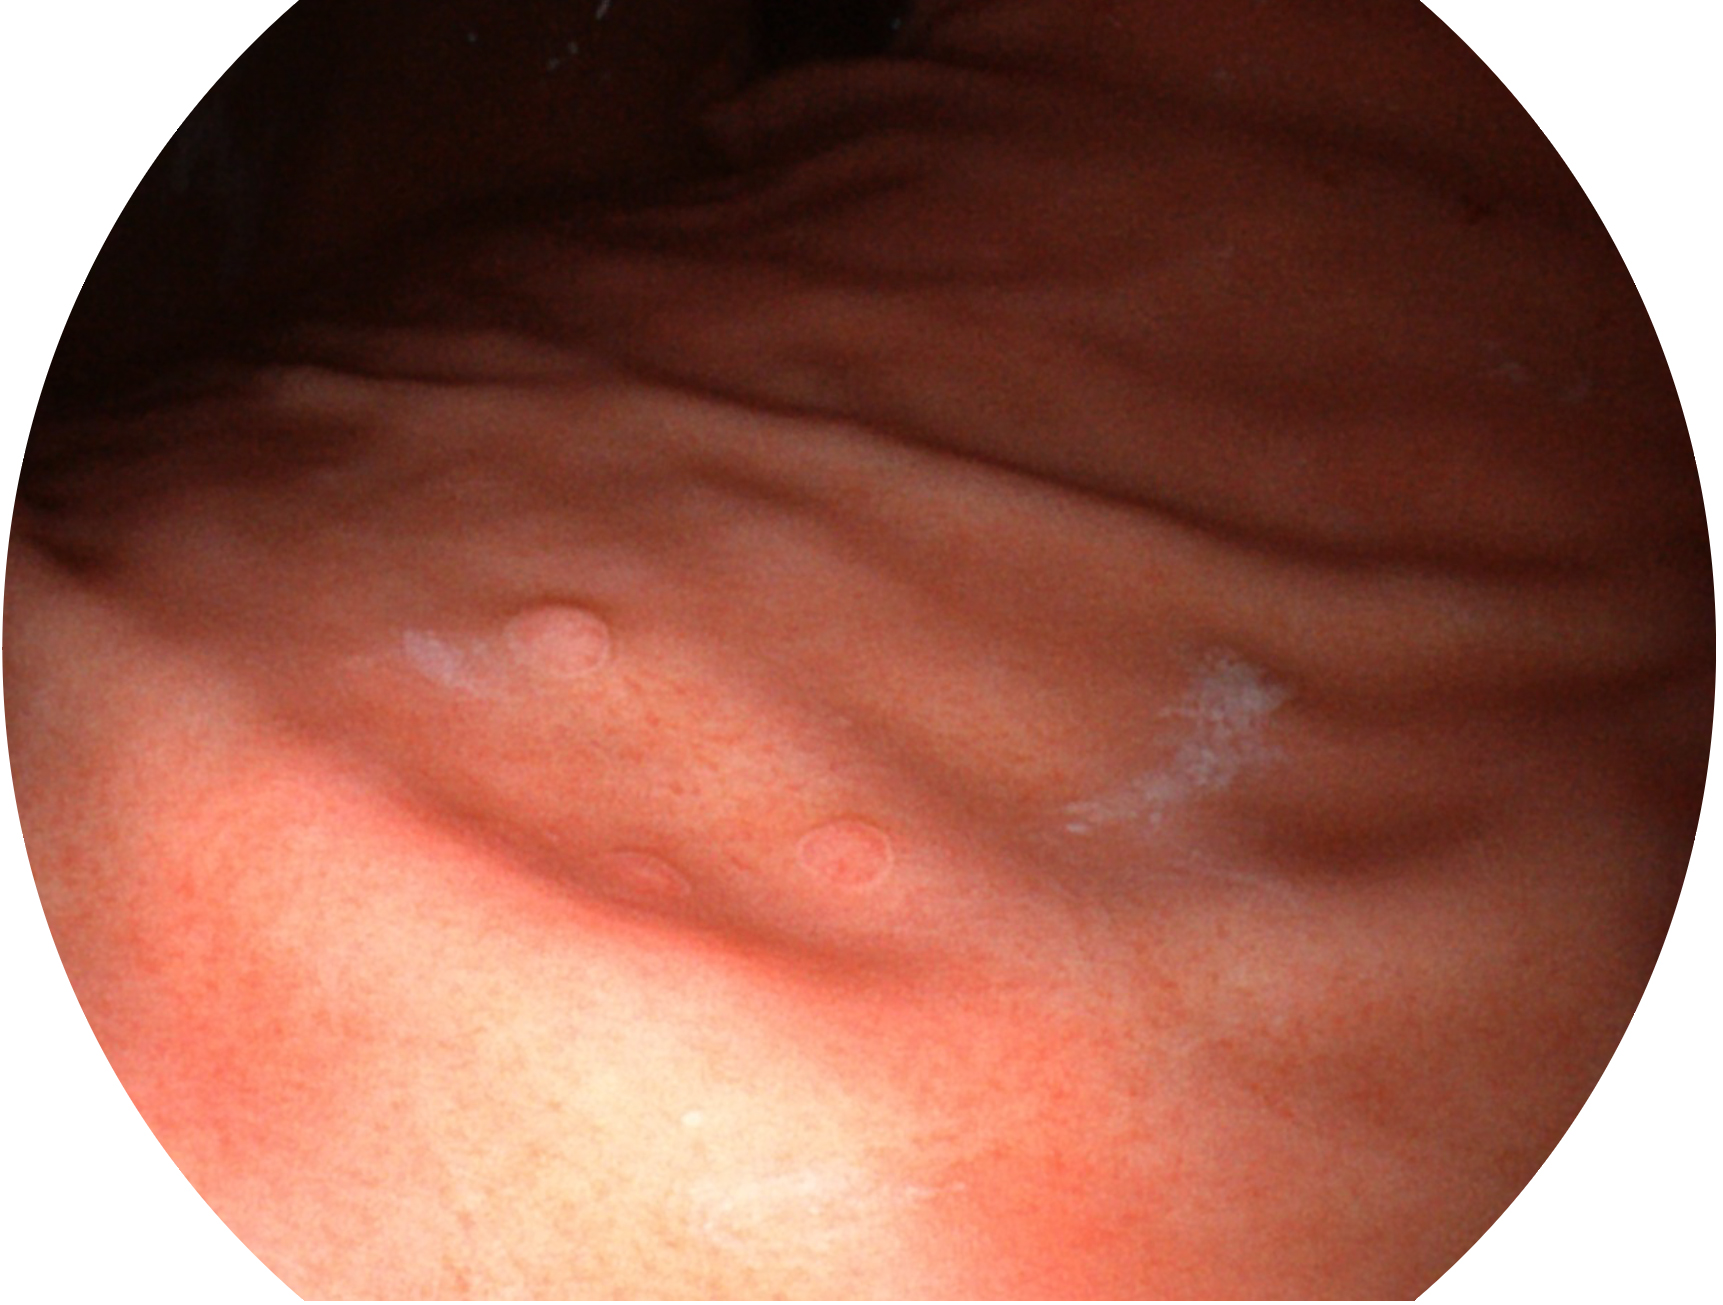

開立新開發(fā)的內(nèi)鏡染色技術(shù),主要是基于多波長(zhǎng)LED 光源的開發(fā),VLS-55Q 四波長(zhǎng)LED 光源是由四個(gè)不同顏色的LED光按照相應(yīng)照明模式所規(guī)定的特定發(fā)光比例進(jìn)行合束后形成,合束后形成的照明光的光譜由紅光、綠光、藍(lán)光及藍(lán)紫光這四個(gè)不同的波段范圍構(gòu)成。具有更高光譜自由度,通過(guò)光譜比例的控制,實(shí)現(xiàn)了聚譜成像技術(shù),英文全稱為“Spectral Focused Imaging, SFI”,縮寫為“SFI”和光電復(fù)合染色成像技術(shù),英文全稱為“Versatile Intelligent Staining Technology, VIST”,縮寫為“VIST”。